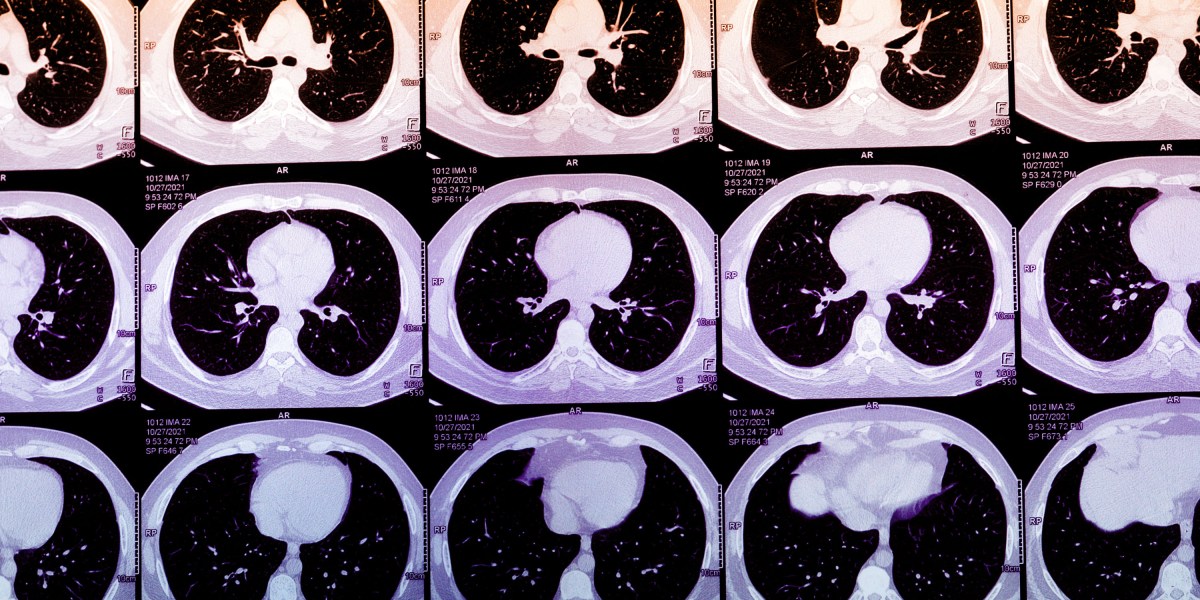

Coronary Artery Calcium (CAC) testing is an underutilized method for assessing heart attack risk. By highlighting the lifecycle of plaque build-up, CAC testing provides crucial insight into cardiac health. Here’s why it matters:

- Access Expansion: New algorithms can derive CAC scores from routine chest CT scans, enhancing accessibility for patients and doctors.